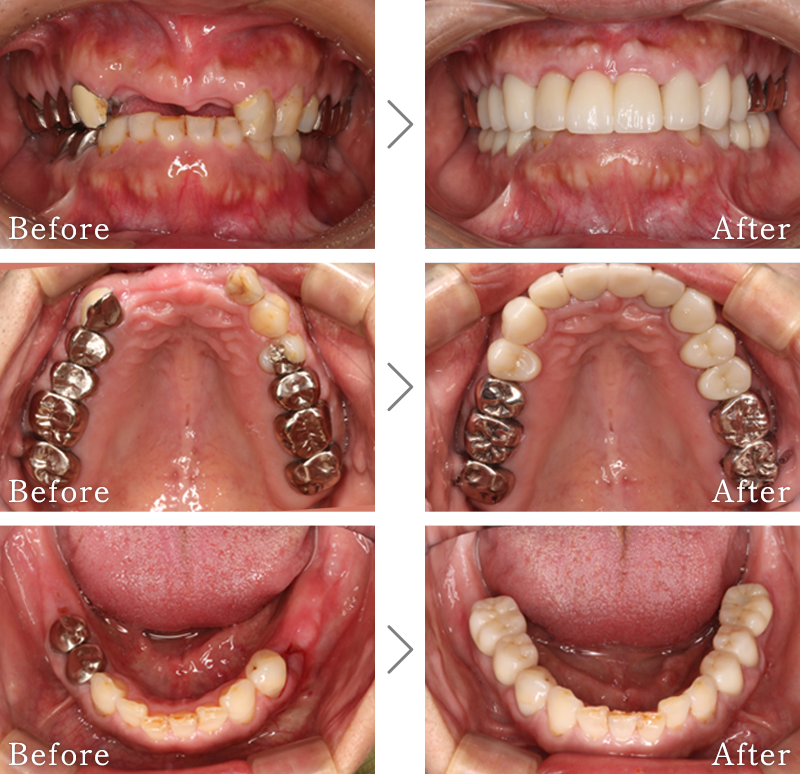

CASE1

主訴 入れ歯も合わず、しっかりと噛んで食事ができないとのことで来院されました。

治療法 上下ともにALL-ON-6と呼ばれる最少本数のインプラントで全ての歯を回復する治療を行なっています。歯の部分は全てセラミックで作成されています。

治療期間 5ヶ月

費用 CT:16,500円(税込)

+ 静脈内鎮静法:77,000円(税込)

+ ALL-ON-6×2:5,500,000円(税込)

合計:5,593,500円(税込)